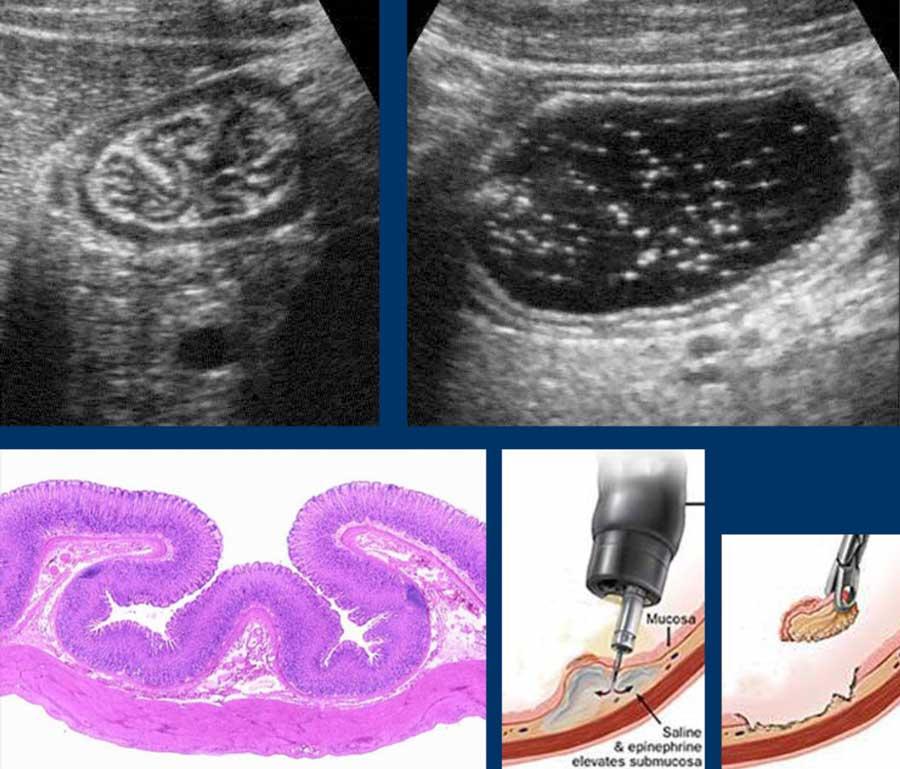

Histology of the GI tract

Từ trong ra ngoài, các lớp của ruột non bao gồm lớp niêm mạc (M.), lớp dưới niêm mạc (S.M.), lớp cơ vòng (C.M.), lớp cơ dọc (L.M.) và lớp thanh mạc (S.)

US fingerprint of the normal GI tract

Cấu trúc năm lớp kinh điển của thành ruột trên siêu âm được hiểu rõ nhất khi quan sát thành dạ dày chứa đầy dịch.

Các lớp, bắt đầu từ trong ra ngoài, có cấu trúc tăng âm-giảm âm-tăng âm-giảm âm-tăng âm hoặc trắng-đen-trắng-đen-trắng.

Superficial mucosa

Lớp niêm mạc nông tăng âm rõ rệt, do chất nhầy và các hạt khí rất nhỏ bị giữ lại giữa các nhung mao ruột non.

Deep Mucosa

Lớp niêm mạc sâu có cấu trúc giảm âm và độ dày thay đổi. Lớp này đại diện cho mô tuyến xếp chặt và – chỉ một phần nhỏ – lớp cơ niêm mạc.

Submucosa

Lớp dưới niêm mạc chứa các mạch máu, dây thần kinh và mô mỡ, có tính chất tăng âm do chứa nhiều mô liên kết lỏng lẻo.

Lớp dưới niêm mạc “kết nối lỏng lẻo” niêm mạc với lớp cơ, và trong quá trình co bóp, lớp dưới niêm mạc có thể được nhìn thấy đi theo các nếp gấp niêm mạc (trên bên trái).

Sau khi uống nước, lớp niêm mạc và lớp dưới niêm mạc được kéo căng và trải phẳng ra (phía trên bên phải).

Mối liên kết lỏng lẻo này cũng giải thích tại sao có thể lấy sinh thiết qua nội soi dạ dày mà không gây hậu quả nghiêm trọng, đặc biệt khi tiêm nước muối sinh lý vào lớp dưới niêm mạc trước (ngay bên dưới).

Muscularis

Lớp cơ có hồi âm thấp do cấu trúc mô cơ và dễ dàng nhận biết như một lớp đen ở phía ngoài.

Nó bao gồm hai lớp: lớp cơ vòng ở trong và lớp cơ dọc ở ngoài, phối hợp với nhau để tạo ra các chuyển động nhu động.

Hai lớp cơ này được ngăn cách bởi một lớp mô liên kết mỏng, chứa mô thần kinh của đám rối Auerbach.